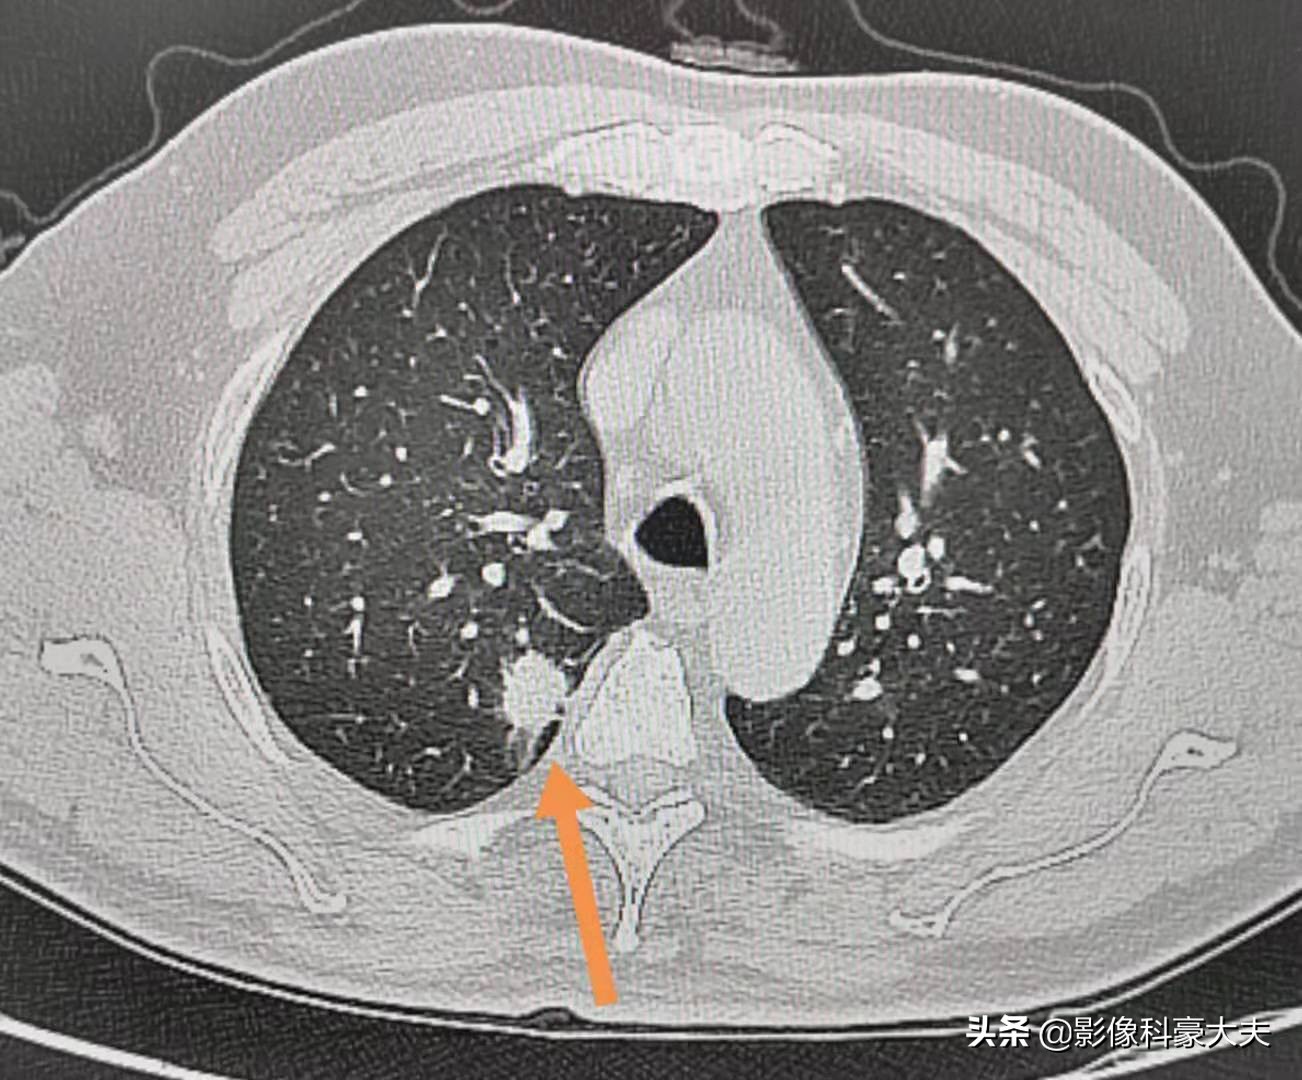

像这个病灶贴近胸膜,是浸润性肺腺癌,低分化,通过胸腔镜微创手术切除,五六天就可以出院。因为肿瘤已经侵犯胸膜,分化也不好,术后做了预防性化疗,5年多没有复发,提示治愈。